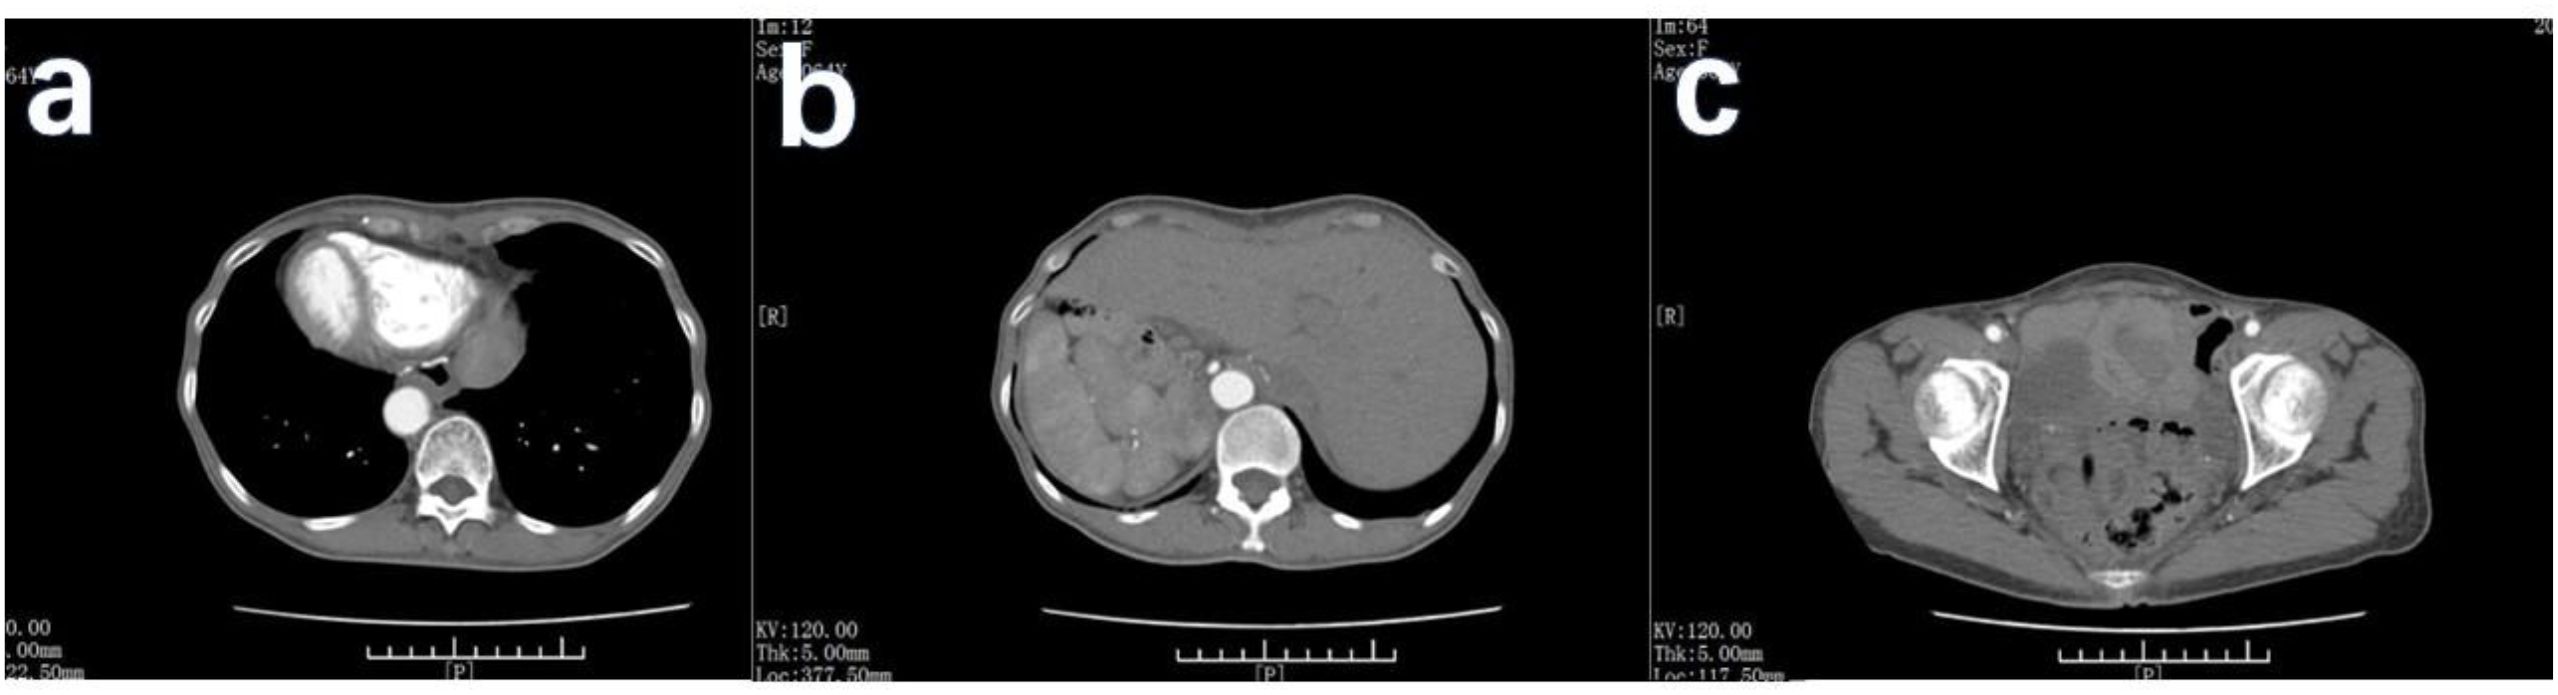

The primary modes of metastasis of gastric cancer are through the bloodstream and lymph nodes. However, in cases such as the Krukenberg tumor (KT), gastric cancer cells can spread to organs within the abdominal cavity and develop implantation metastases. This report describes the treatment process for a patient with situs inversus totalis (SIT), gastric cancer, and a KT. A 63-year-old woman with SIT presented with abnormal vaginal bleeding and was diagnosed with gastric cancer with KT. After careful evaluation, the patient underwent total gastrectomy (Roux-en-Y esophagojejunostomy, antecolic, and D2 lymph node dissection), total hysterectomy plus double adnexectomy, and appendectomy. Considering the patient's SIT, we devised a modified surgical strategy. The surgery was successful. Postoperative adjuvant chemotherapy was administered, and her current evaluation indicated stable disease. Although gastric cancer complicated by KT is rare, it occurs in some cases. Surgical treatment should be considered if both the primary and secondary lesions can be radically resected and supplemented with systemic chemotherapy. For patients with SIT, the surgical approach should be appropriately adjusted with careful preoperative evaluation to ensure procedural safety.